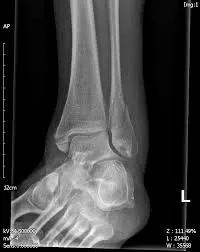

3. Beeldvorming: er wordt een röntgenfoto van de enkel gemaakt om de diagnose te bevestigen. Hierop is de enkelbreuk zichtbaar en kan de arts beoordelen wat voor type breuk het is. Soms wordt een CT-scan gedaan om de details van de breuk en eventuele gewrichtsschade beter in kaart te brengen, vooral bij complexe enkelfracturen.